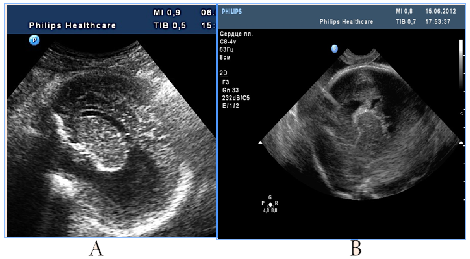

All cases with prosencephalic malformations had an adverse catamnesis connected with combined pathology. Two cases of alobar holoprosencephaly (HPE) and syndromic semilobar HPE were connected with perinatal losses. Syndromic lobar HPE with partial callosal agenesis and septo-optic dysplasia didn't have perinatal consequences, but the clinical outcome for the child was unfavorable as well (Figure1). HPE in 3rd trimester, 4 cases:

Figure 1 HPE in 3rd trimester, 4cases.

А) Alobar syndromic HPE with the residual mantle of the cortex at the base of the brain, severe progressive disgenetic hydrocephalus with macrocrania, intranatal death, clinical intranatal mismatch of head and pelvic size, fetus-damaging operation.

B) Isolated alobar HPE, cup-shaped type, the biggest part of the cortical mantleis attended, but it does not cover a single ​​anterior ventricular area, infant death.

C, D, E). Semilobar syndromic HPE with callosal agenesis. The ventricles are connecting through a narrow channel across the midline, thalamuses partially fused, IUGR, absent umbilical end-diastolic flow, antenatal death.

F). Fetal NSG and MRI of the newborn with syndromic lobar HPE, partial callosal agenesis, septo-optic dysplasia, US variant with merged, widely separated narrow acute-angled anterior horns of ventricular and dilated Verga’s cavity, long-term neurological disorders, severe visual impairment, epilepsy in the kid.